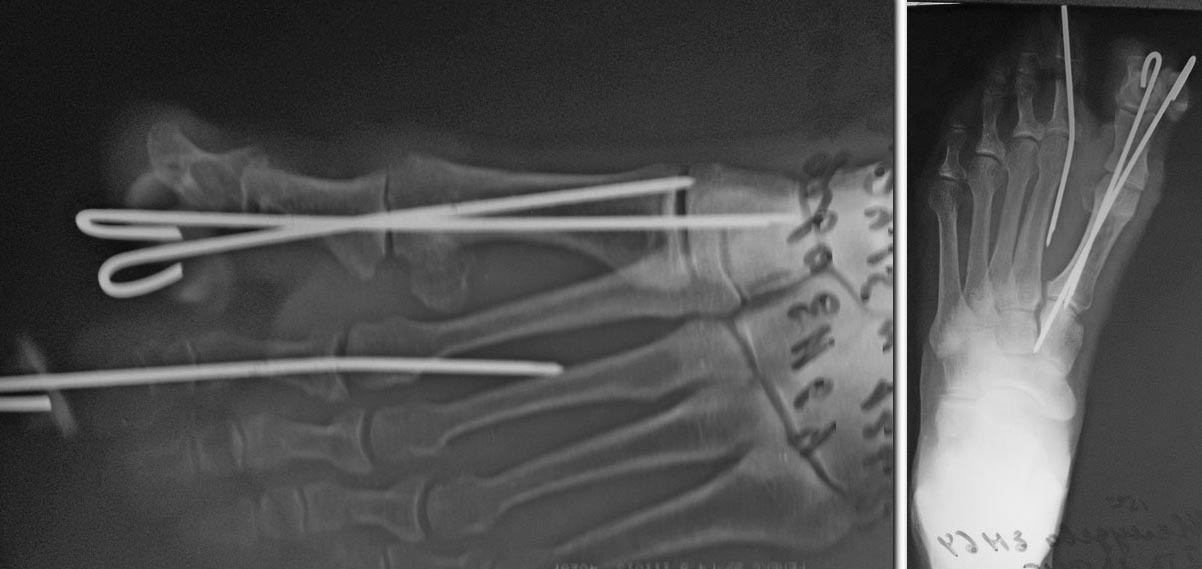

Прооперировали